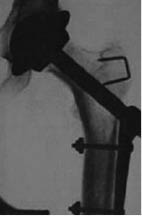

En 1938, en Londres se realiza la primera sustitución de cadera de componentes emparentados con acero inoxidable en seis pacientes con enfermedad de Still por parte de Philip Wiles (Figura 4).13 Él presenta una prótesis bicompartimental la cual se basaba en un elemento de cabeza femoral compuesto por un tallo, una placa lateral y tornillos y una unidad acetabular que se estabilizaba con un tornillo, siendo la prótesis no cementada primigenia; sin embargo, para Wiles la Segunda Guerra Mundial se interpuso en el desarrollo de su técnica y materiales. En los años 40 se crea la primera prótesis parcial utilizada por parte de Bohlman y Moore (Figura 5) en un paciente que había tenido una resección femoral proximal por tumor de células gigantes, era una pieza de endoprótesis de vitalio, con buena respuesta de 75% de movilidad.14

Las prótesis articulares han revolucionado la ortopedia conocida desde su creación, modificando la historia y dando una resolución a patologías que antes no tenían un gran pronóstico, a pesar de iniciar como tratamiento de otras enfermedades infecciosas, pasar por un proceso de ser la alternativa de fracturas y llegar hasta la actualidad donde son la principal alternativa de tratamiento para enfermedades crónico-degenerativas articulares (Figuras 10 y 11).